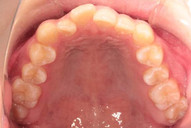

診断名 : 叢生(歯の凸凹) ・過蓋咬合(咬むと下の前歯が見えない)

治療内容:上下歯列の拡大→下奥歯後ろに移動→バイトターボと顎間ゴムで併用